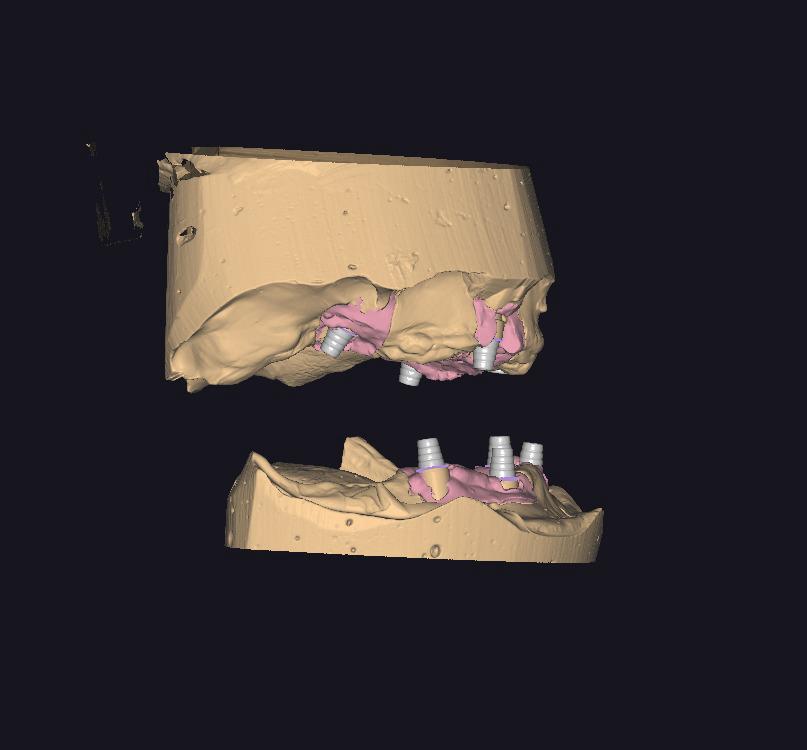

HYBRID PROTEZLER

HYBRID CAM CAM CrCo & TITANYUM PORSELEN BITIM

HYBRID CAM CAM CrCo ARA cOvDE PORSELEN BITIM

HYBRID CAM CAM CrCo TiTANYUM BiTIMSIZ KRON

HYBRID cam cam CrCo BITIMSIZ KRON ARA GOVDE

VIDALI IMPLANT USTU BAR (HER ABUTMENT BAŞI)

CAD CAM CERRAHI PLAK